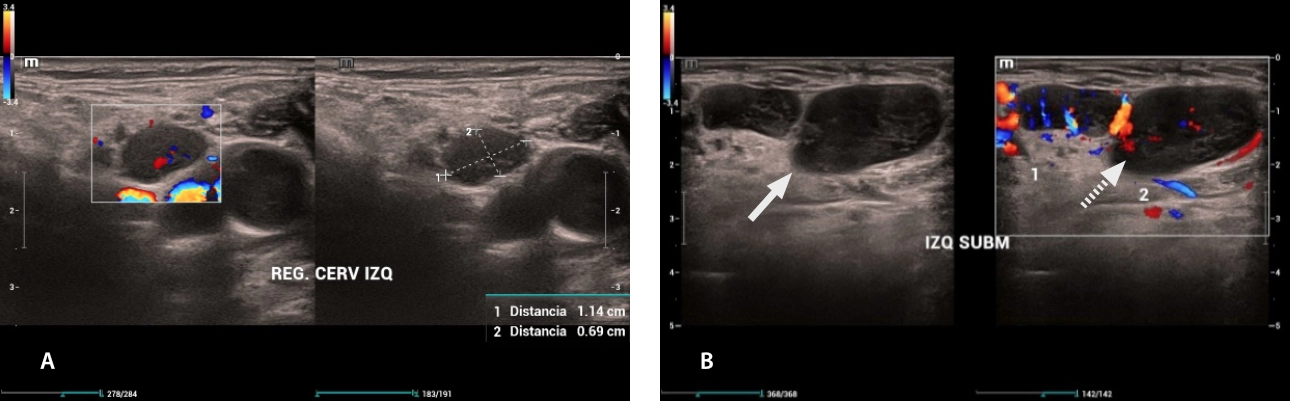

Fig. 5 Multiple cervical lymphadenopathy: (A) Left laterocervical lymphadenopathy (B) Left submandibular lymphadenopathy: rounded morphology, with loss echogenic fat center on grayscale (white arrow), loss of vascular hilum on color Doppler (dashed arrow).